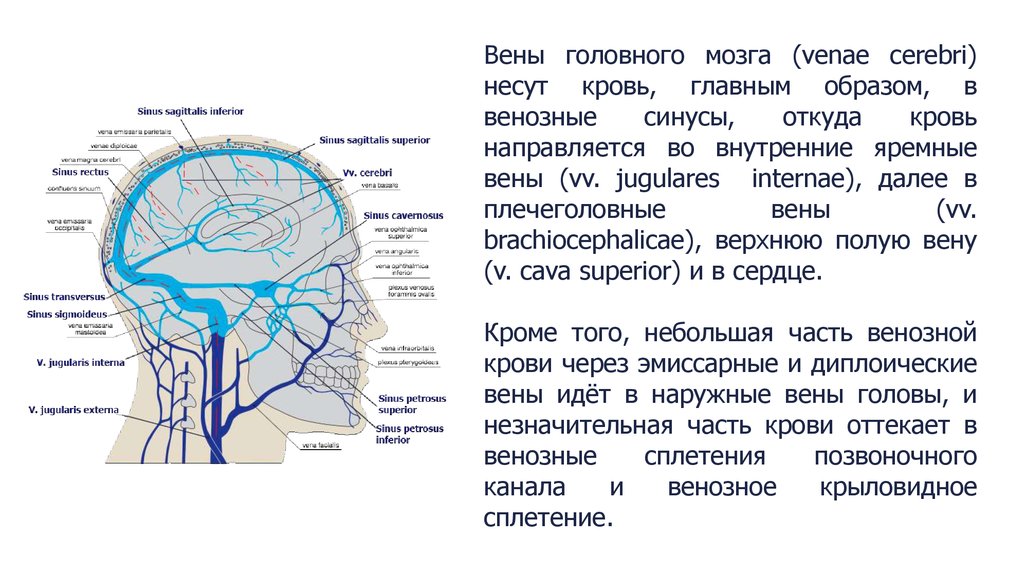

Анатомия внутренней яремной вены: КТ изображения